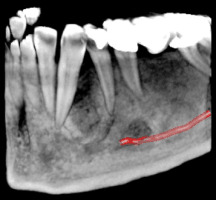

3D скенер на зъби – една челюст

Триизмерният образ на цяла челюст (горна или долна) позволява анализ на различни патологични състояния в челюстта като възпаления, тумори, кисти, фрактури и др. Използва се широко при поставянето на няколко импланта на едната челюст, определяне на точното положение на ретинирани зъби, както и за изработка на хирургични водачи.